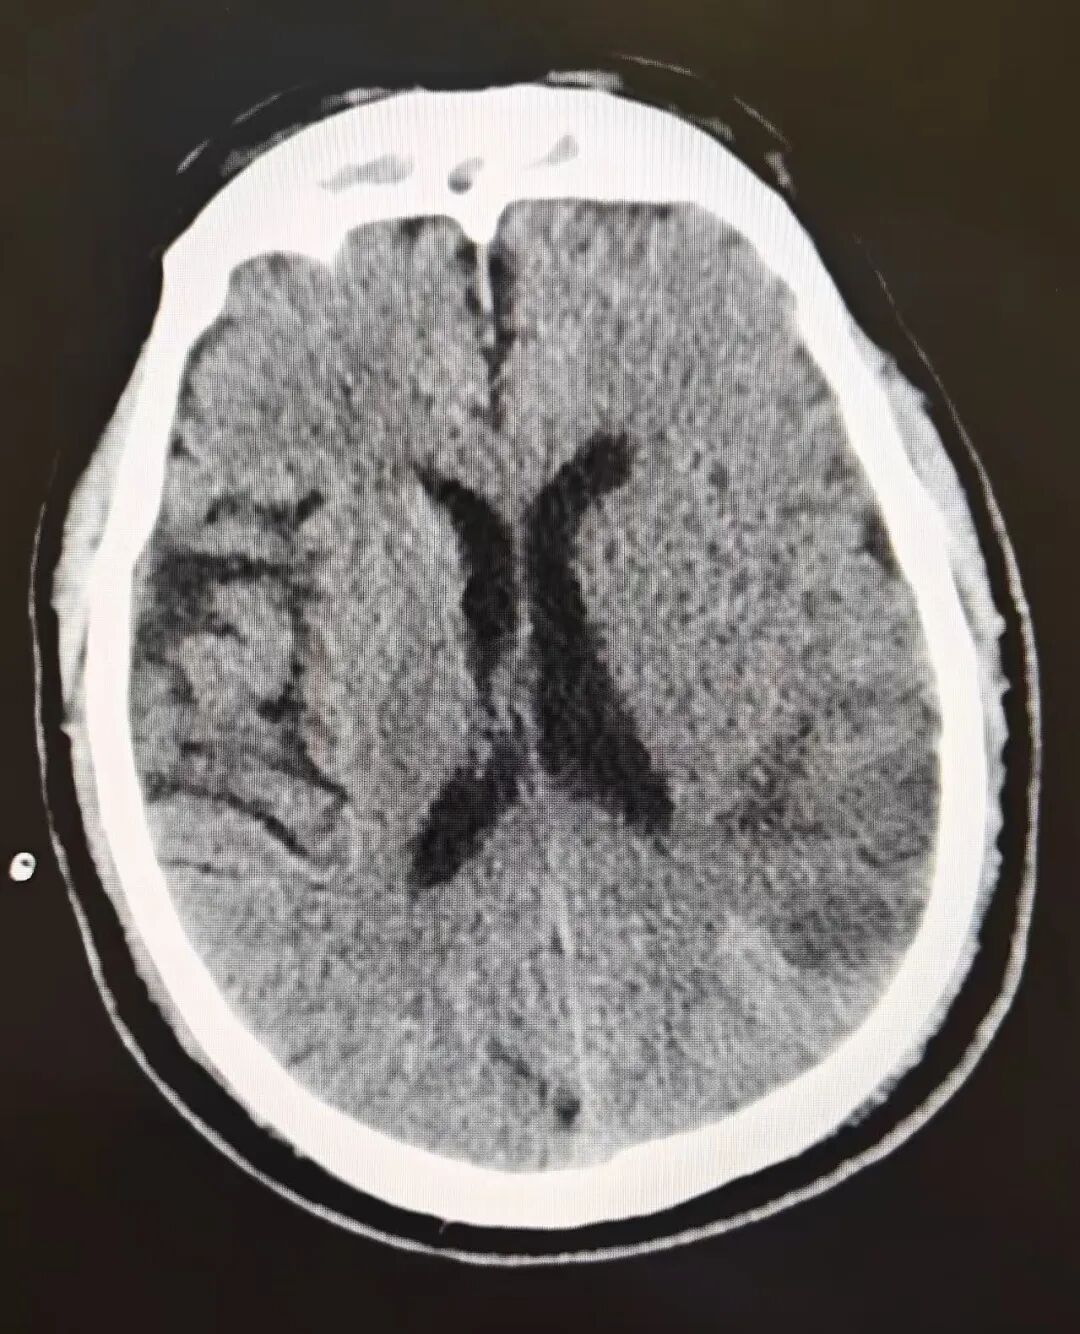

当晚,一名患者因急性颈内动脉闭塞突发重症脑梗死被紧急送入医院。颈内动脉作为脑部重要供血血管,一旦闭塞,每延误1分钟,就会有大量脑细胞坏死,救援时间极为紧迫。

接到急诊通知后,西安市中心医院经开院区迅速启动卒中急救绿色通道,多学科团队同步响应、无缝衔接。急诊科医护人员第一时间接诊患者,迅速完成生命体征监测与初步评估;放射科立即开通专属检查通道,加急进行头颅影像检查,精准锁定闭塞血管位置;检验科争分夺秒开展凝血、生化等关键指标检测,为后续治疗提供数据支持;药剂科迅速调配急诊溶栓药物,确保“药等人”,而非“人等药”。

明确患者符合急诊溶栓指征后,该院神经外科团队果断实施急诊溶栓治疗,为血管再通争取宝贵时间。溶栓治疗后,团队根据患者病情,进一步制定“急诊脑血管造影 + 动脉取栓”的精准治疗方案。